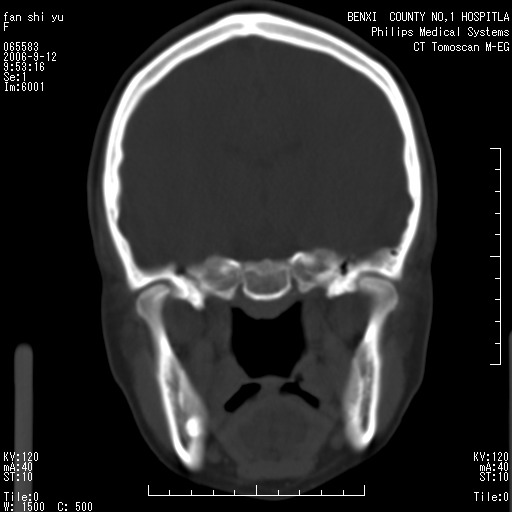

标题: CT4607:看看这个头颅冠状位。

女,22岁,自觉头顶部质硬包块.

考虑蛛网膜粒压迹

巨大蛛网膜粒压迹。

为何没有轴位扫描 考虑蛛网膜囊肿压迹 可mr检查确诊